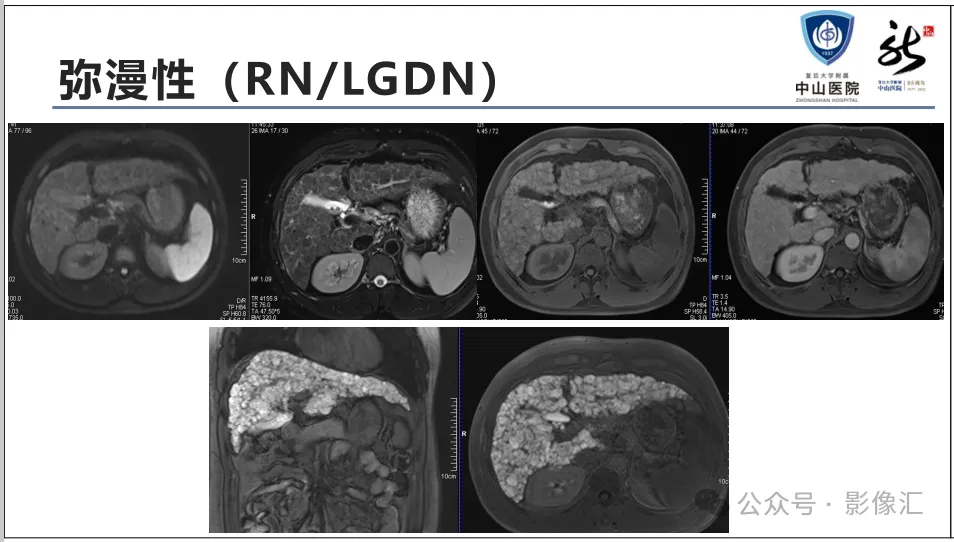

肝胆特异性对比剂增强肝胆图像判读方法与策略,课件来源于网络,作者复旦大学附属中山医院放射科饶圣祥教授。